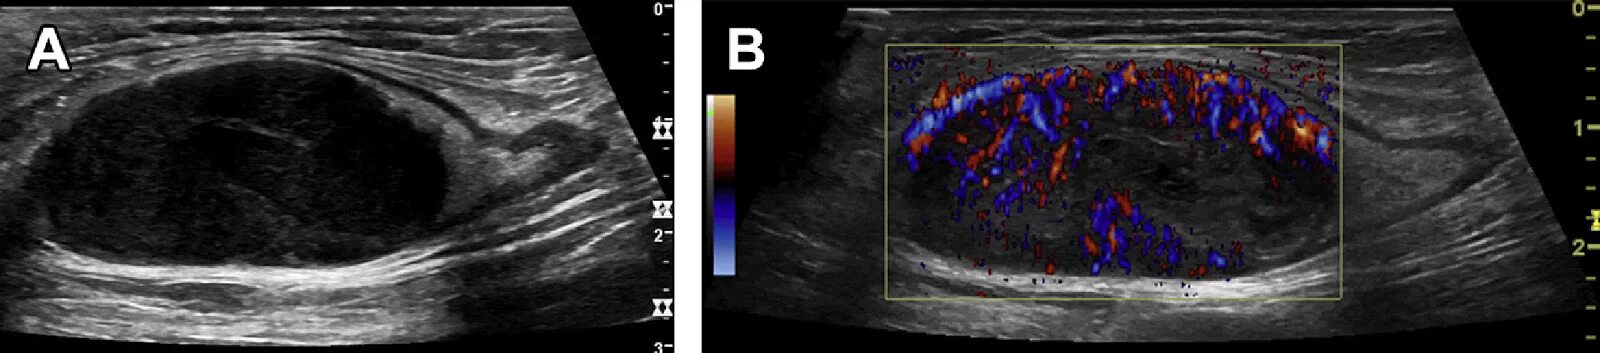

Метастазы в паховых лимфоузлах